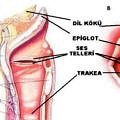

Larenks enfeksiyonların tanı ve tedavisiLarenks hastalıkları çok geniş bir semptom ve bulgu spektrumuna sahiptir. Ses kısıklığı en sık rastlanılan semptomdur. Öksürük, ağrı, stridor, afoni ve dispne diğer görülebilen semptomlardandır. Bununla beraber etkene göre sistemik belirtiler de gözlenebilir.

Larenks enfeksiyonların tanı ve tedavisiLarenks hastalıkları çok geniş bir semptom ve bulgu spektrumuna sahiptir. Ses kısıklığı en sık rastlanılan semptomdur. Öksürük, ağrı, stridor, afoni ve dispne diğer görülebilen semptomlardandır. Bununla beraber etkene göre sistemik belirtiler de gözlenebilir.